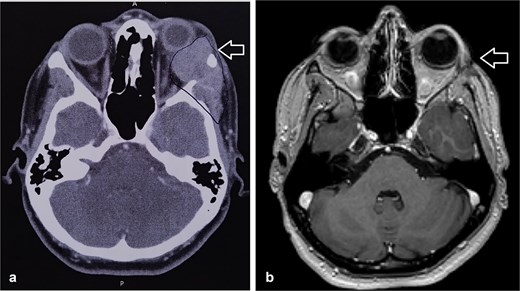

She was kept on follow-up for four years with clinical exams and MR imaging until she felt a palpable mass at the left lower dental root with local disease recurrence on orbit MRI (Fig. 3). An excisional biopsy from the submandibular mass revealed ACC, indicating metastatic disease. She was consequently given five cycles of paclitaxel and carboplatin chemotherapy.

Orbit MRI showed lobulated well-defined lesion, hyperintense to intermediate on T2W (a), hypointense on T1W (b) structures with cystic changes measuring 2 × 1.5 cm and 2 × 1.2 cm. After IV contrast administration they showed heterogeneous moderate enhancement.

MRI is the preferred modality to detect bony invasion and perineural spread. ACC usually appears as T1 isointense and T2 hyperintense with enhancement . Our patient's orbit MRI showed a lobulated, well-defined lesion, hyperintense to intermediate on T2W and hypointense on T1W structures with cystic changes.